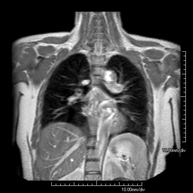

- RM del Mediastí

Prova diagnòstica no invasiva que consisteix en l'obtenció d'imatges d'alta definició anatòmica del mediastí mitjançant l'ús d'un camp electromagnètic i ones de ràdio (amb un emissor i un receptor). No utilitza radiació ionitzant. El mediastí és la part central de la caixa toràcica que inclou el tim, els grans vasos (aorta toràcica, vena cava inferior i superior, etc.), el cor, la tràquea i els bronquis principals, els ganglis limfàtics mediastínics i hilars, l'esòfag, etc. Està especialment indicada en lesions mediastíniques per diferenciar si són quístiques o sòlides, en el diagnòstic diferencial de les lesions del mediastí anterior, etc. De vegades s'ha d'emprar contrast paramagnètic (Gadolini) per completar l'estudi. - RM Tòrax